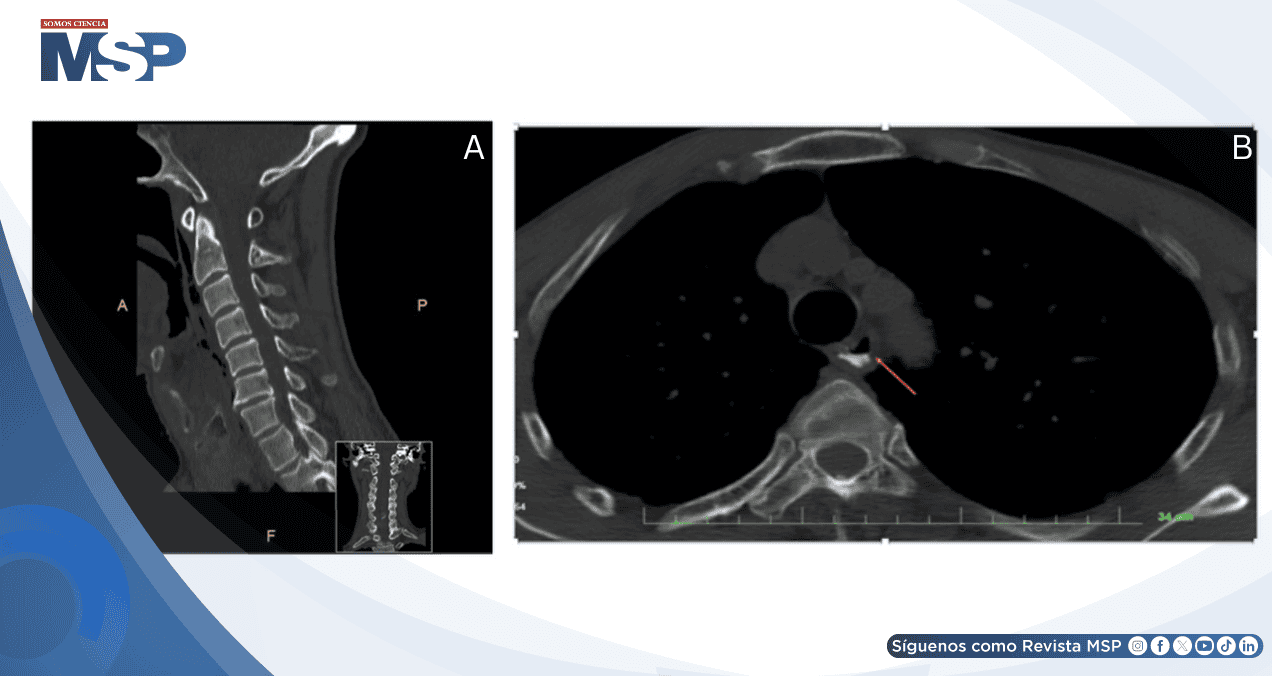

Los estudios de imagen fueron fundamentales para el diagnóstico. La tomografía computarizada de columna cervical mostró cambios degenerativos sin fracturas, mientras que la esofagografía con contraste de gastrografina demostró irregularidades en la pared esofágica proximal con extravasación del medio de contraste hacia el espacio extraluminal.

Se identificaron densidades de gas en los espacios retrofaríngeo y paravertebral, confirmando la perforación esofágica. La laringoscopia directa bajo anestesia general permitió visualizar una ruptura de 2.5 cm en la pared posterior de la hipofaringe.